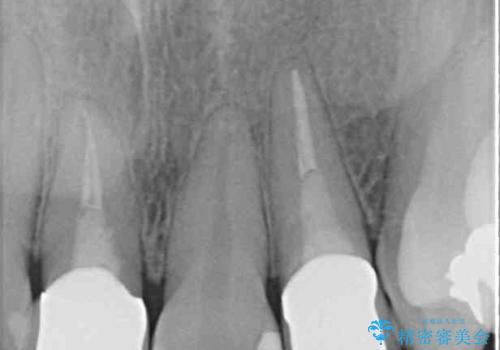

- 20年ほど前に被せた前歯のメタルボンドクラウンの色合いを気にして来院された患者様です。

2歯をオールセラミッククラウン(ジルコニアクラウン)にて補綴することとしました。

裏打ちが金属の場合、どうしても金属色を遮蔽しないとならないため、透明感のない色合いとなってしまいます。

土台の金属はグラスファイバーを含有したものに、クラウンの土台は強化セラミックとすることで、自然な前歯に仕上がりました。